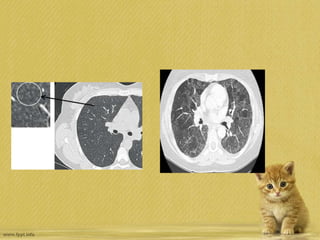

• Typicalcomputedtomographyfeaturesofacu

terespiratorydistresssyndromeshowing:no

n-homogeneousdistribution,aventro-

dorsalgradientofdensity,moredenseconsoli

dationinthedependentregions,widespreadg

round-

glassopacitiesassociatedwiththickeningofin

terlobularsepta(crazypaving),andpleuraleff

usion.